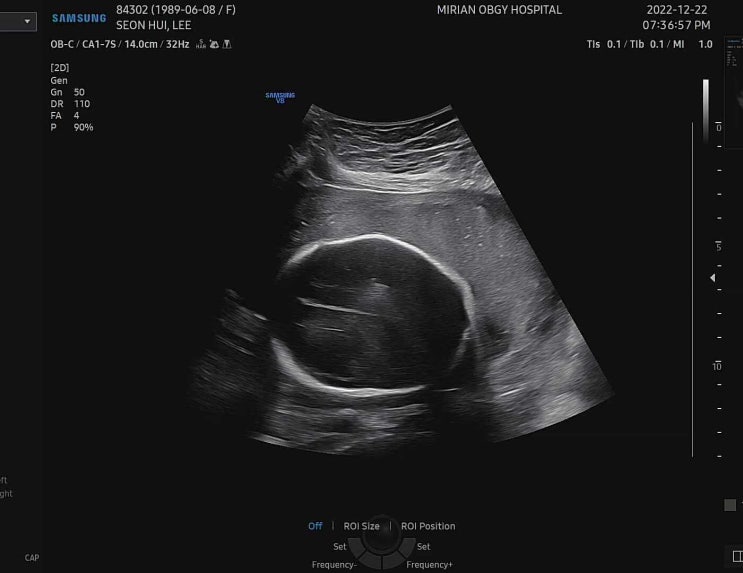

30주 5일 초음파

오늘은 정기검진날! 30주 5일 1.5kg정도 백일해주사 접종완료 다담주 검진땐 신랑도 맞혀야지 질염은 여전...

27주 4일 초음파

27주 4일 약 1kg 제법 묵직하다 다리는 왜 아직 짧은겨..? 길어지게찌...?